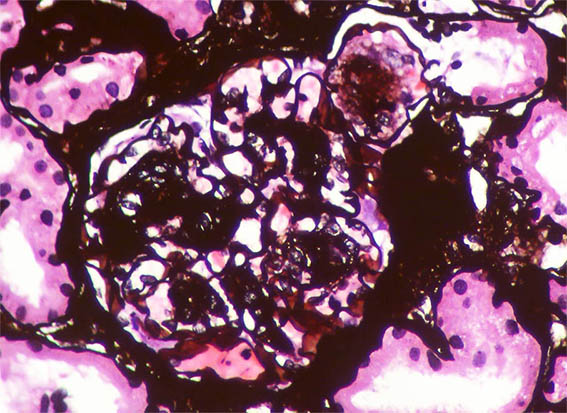

Figura 8. Plata-metenamina, X400.

Figura 9. Plata-metenamina, X400.

Figura 10. Plata-metenamina, X400. Observe el nódulo de la parte superior derecha, rodeado por membrana basal (posiblemente microaneurisma con trombo en organización).